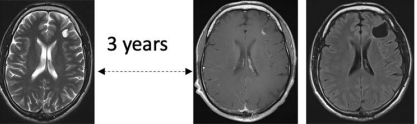

另外一例的进展也很突然:偶然查出时,选择随访,始终未见肿瘤体积增大;然而,第 3 次随访MRI却意外出现局灶性对比增强,遂决定立即手术。